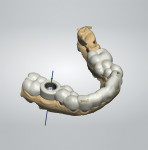

A CBCT image (Figure 2) and digital impression (Figure 3) were obtained for diagnosis and treatment planning. To facilitate this, the CBCT image and impression were merged into the implant planning software for evaluation. Tooth No. 30 was removed from the virtual model, and a virtual restoration was created (Figure 4). Next, the vital structures and osseous anatomy were identified, and a virtual implant was planned (Figure 5 and Figure 6). A virtual fully guided surgical template was created (Figure 7) and then sent to the in-office printer for guide fabrication (Figure 8 and Figure 9). Using a flapless technique, the crown of tooth No. 30 was removed, and the necrotic roots were sectioned and surgically removed (Figure 10 and Figure 11). Following this, the CT template was placed, the osteotomies were completed, and the implant was placed in a guided fashion with 60 Ncm of torque (Figure 12 and Figure 13). After the osseous socket was grafted with allogenic bone, a healing abutment was placed, and the tissue was stabilized without mobilization using 3-0 chromic sutures (Figure 14 and Figure 15). An immediate post-operative CBCT scan was used to verify that the implant was placed as planned (Figure 16 and Figure 17).

At 8 weeks following placement, the implant was confirmed to be osseointegrated. A final digital impression was obtained during the same visit using a scan body to capture the implant position (Figure 18). Next, the digital impression was uploaded to Artistic Dental Studio for fabrication of a model-less, screw-retained monolithic zirconium crown, which was delivered to the patient at 9 weeks following implant placement. The implant was ideally placed creating a centric screw access and well-supported ceramics for long-term predictability (Figure 19 through Figure 21).